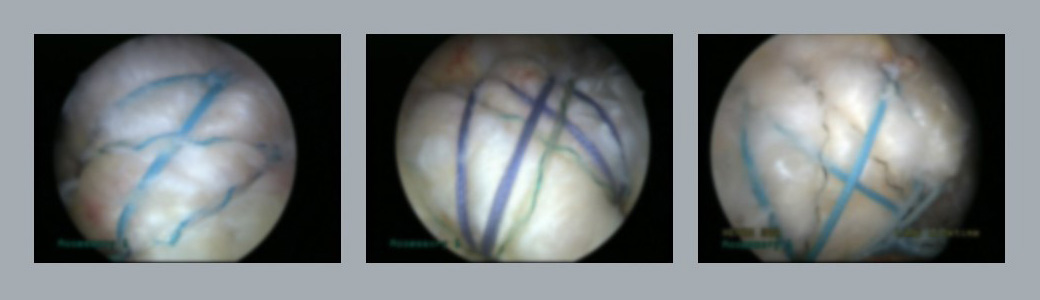

관절 내시경적 회전근개 봉합술은 가느다란 관절경을 이용해 끊어진 힘줄의 위치를 확인 후

실이 달린 나사를 통해 파열된 회전근개를 뼈에 다시 붙여줍니다.

실이 달린 나사는 영구적으로 녹지 않고 몸 안에 있게 됩니다.